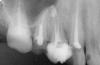

Елена Резник Опубликовано 13 марта, 2010 Автор Поделиться Опубликовано 13 марта, 2010 Имплантов, как я поняла, нужно два, а это дороговато получается.А Вы считаете импланты на много лучше?Много начиталась всякого и стало страшновато. Делаю не в "крутом" медцентре, про врача и оборудование ничего практически не знаю, кроме того, что "кто-то что-то" уже там делал, поэтому трудно решиться на импланты. Да, собственно, поэтому и прошу совета. Снимок покрупнее прилагаю. Ссылка на комментарий

Sir Edward'S Опубликовано 14 марта, 2010 Поделиться Опубликовано 14 марта, 2010 У меня пришеечная облась желтеет, коричневеет, а потом начинает пропадать эмаль. Получается такая тонкая темно коричневая полоска около десен. Говорят что это флюороз.А на счет прикуса, тот врач имел ввиду, что верхний ряд, ввиду отсутствия нижних зубов опустился, хотя на тот момент с удаления нижней 6 прошло только пол года.Теперяшний врач сказал, что "укоротит" верхние, и все будет ровно, собственно для этого и сказал их депульпировать. Они сильно коричневые, но эмаль пока на месте. Посмотрите по снимку, так действительно можно сделать? А то депульпирую, а потом ничего не получится. в дополнение к панорамному снимку желательно увидеть прицельные снимки верх справа 3,4,5,6; верх слева 3,4 . еще желательно их фото .если зубы разрушены под десну то их восстановление может быть проблематичным . Ссылка на комментарий

annda Опубликовано 18 марта, 2010 Поделиться Опубликовано 18 марта, 2010 Была сегодня у терапевта, забрала прицельные снимки, но они, к сожалению, оказались до штифтов. Но терапевт сказала, что штифты титановые и стоят "намертво", и очень ругалась, что я дала рассверлить 5-ку. По поводу оставшегося куска штифта, сказала, что если нормально вкладку сделают, то ничего страшного быть не должно. Так что я немного успокоилась.Буду ждать когда изготовят вкладки. Извиняюсь, если кого обидела, всех благодарю за отзывчивость, будет завершена подготовка, обязательно сделаю снимок, может еще советы понадобятся.Титановые штифты не ломаются,да и по снимку анкер латунный в 5ке(только ИМХО) Ссылка на комментарий